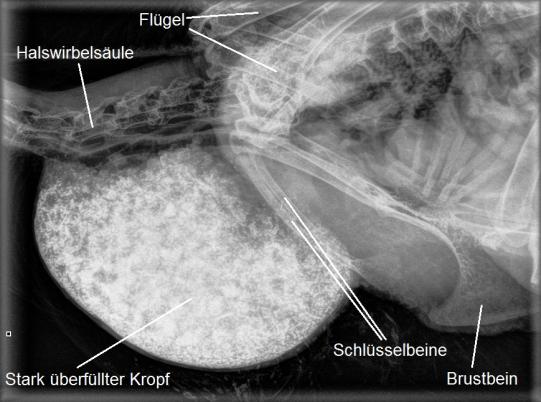

In der Vorderbrustregion findet sich eine kinderfaustgrosse Masse, welche sich anfühlt wie eine mit Sand gefüllte Socke. Das Huhn ist stark abgemagert und besitzt praktisch keine Brustmuskulatur mehr - ein Zeichen, dass es sich schon längere Zeit nicht mehr richtig ernähren konnte. Im Röntgen bestätigt sich der Verdacht einer Kropfanschoppung: Das Organ ist stark vergrössert und enthält eine grosse Menge mineraldichtes Material - höchstwahrscheinlich Sand. Offensichtlich ist diese Anschoppung verantwortlich dafür, dass die aufgepickten Körner nicht in die Mägen weitertransportiert sondern wieder ausgewürgt ("regurgitiert") werden und Susi so droht, zu verhungern.